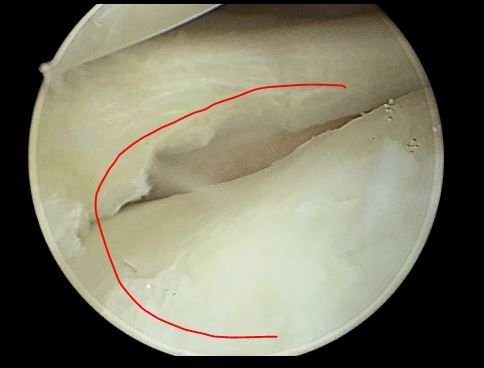

2,女性,32 岁,右膝关节反复弹响,膝关节交锁、疼痛、肿胀。

关节镜下见外侧半月板大厚, 完全覆盖胫骨平台

半月板内部分层撕裂

中央部撕裂